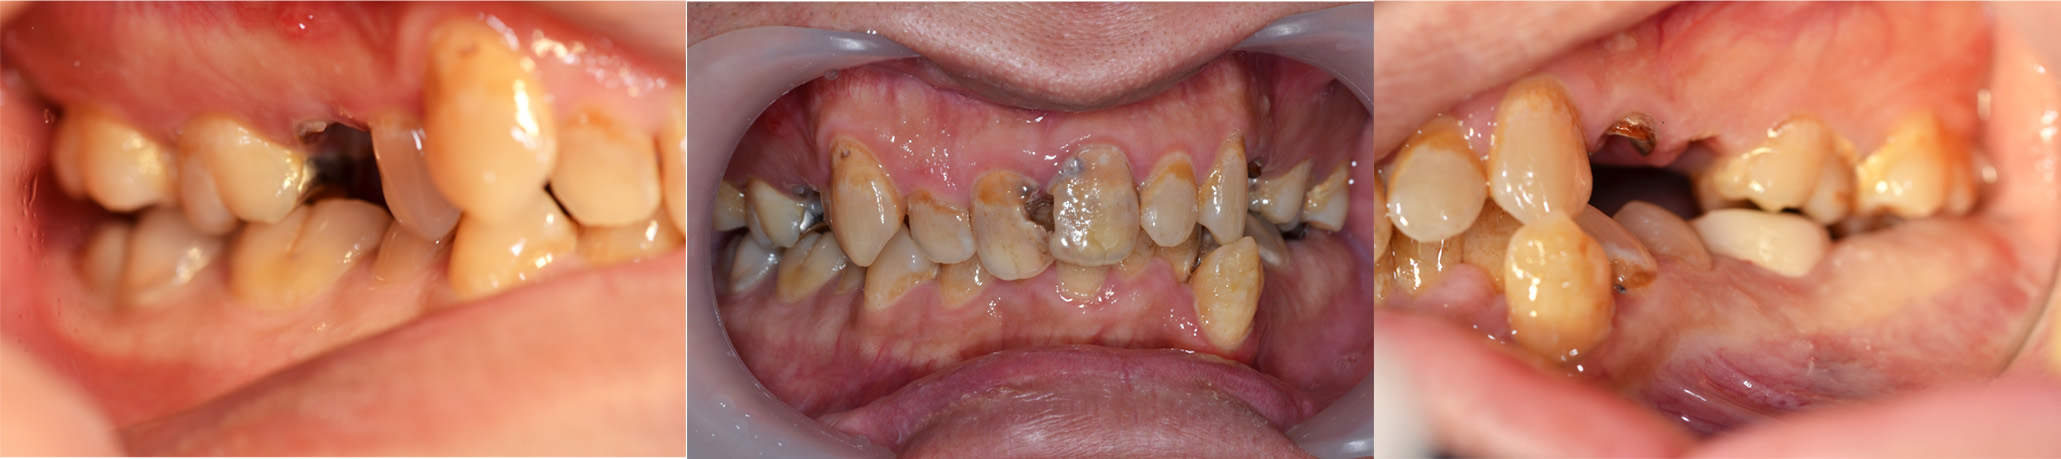

| 術前 |

年齢:36歳

主訴:歯が痛い

初診時の診断と治療方針

初診時の口腔内写真です。主訴の歯の痛みは、斜めに生え噛む面が虫歯になっている右下親知らずであることが分かります。また、その他の部位にも多くの修復物や歯列の乱配を認め、う蝕と歯周病共にリスクが高いことが考えられます。

さらに、歯列の乱配だけでなく傾斜、はまり込みを認めます。 X線写真では全顎的な軽度の歯周病の進行、左下には歯根の著しい吸収を認める乳歯も残っています。引き続き医療面接、う蝕や歯周病の詳しい検査を進め、治療方針についてカウンセリングを行った結果、患者様は顎関節の不調も感じており、インプラントや矯正を含めた全顎的な咬合治療を行っていくことになりました。